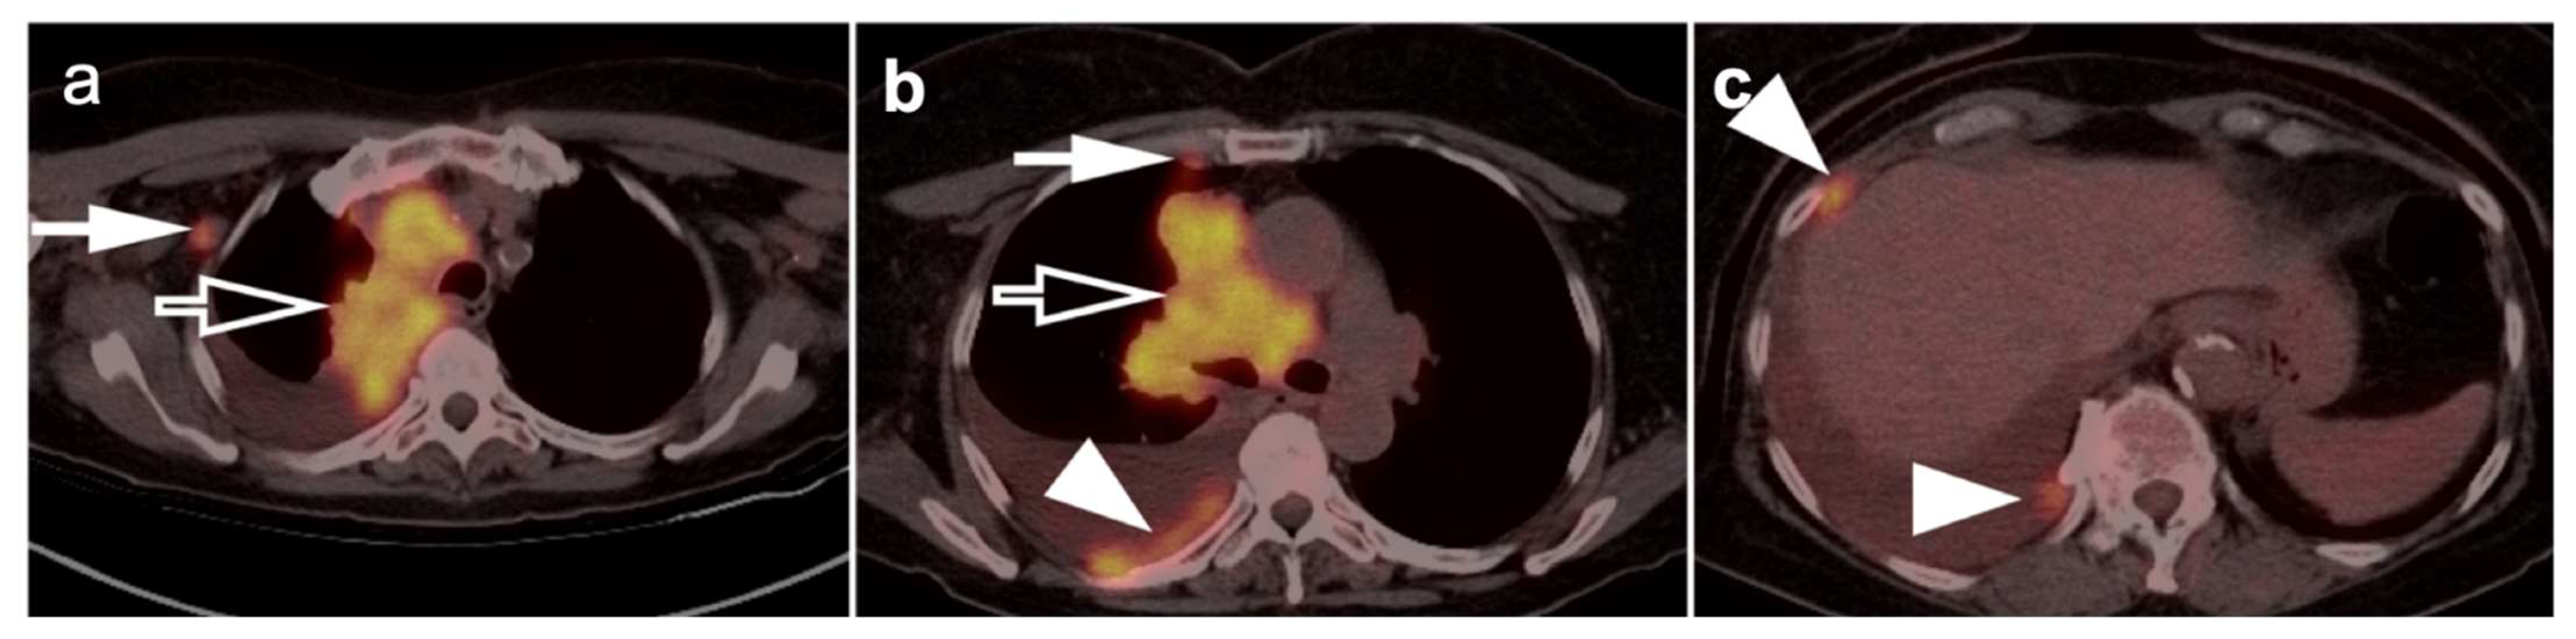

N staging identifies nodal involvement in lung cancer is of paramount importance, especially in patients with mediastinal disease without distant extra-thoracic disease. In these patients, the N stage will have therapeutic and prognostic implications [29]. In describing areas of nodal involvement, it is important to identify the specific nodal location involved, as outlined by the IASCL, as this will affect the N classification [26]. Patients staged as N0 or N1, without lymph node involvement, are generally treated with local intervention, and patients with N2 disease with ipsilateral mediastinal lymph node metastases might benefit from a combined approach with local and systemic therapies. N3 diseases with contralateral mediastinal lymph node metastases are considered incurable and will eventually require palliative care [2]. FDG PET-CT has advantages over CT alone, even when the lymph nodes are smaller than 10 mm in diameter [2,30]. FDG PET-CT is of crucial importance in evaluating nodal sites that are inaccessible to mediastinoscopy, such as the aortopulmonary window, anterior mediastinum, and posterior subcarinal nodes. Even though FDG PET-CT is an excellent noninvasive imaging modality in the detection of nodal metastatic involvement, mediastinoscopy remains the gold-standard and needs to be performed wherever there is ambiguity or uncertainty with regard to the status of any one lymph node in patients with NSCLC (Figure 9).

Nearly half of all patients with NSCLC have distant metastatic disease at initial diagnosis and identification of distant metastases is of major importance in the management and prognosis. Additionally, among patients who have been treated with radical and supposedly curative therapy, approximately 20% are likely to develop recurrent disease due to undetected foci of metastasis at initial M staging. Distant metastases are most commonly seen involving the brain, skeleton, liver, and adrenal glands in descending order of frequency (Figure 10) [31]. Traditional evaluation for distant metastatic disease includes CT scans of chest, abdomen, and pelvis, brain imaging with CT or MRI and bone scintigraphy [2]. However, FDG PET-CT has been shown to be great utility in M staging of the patients with NSCLC, specifically if the patients present with clinical manifestations of metastatic disease. Additionally, FDG PET-CT has been shown to provide more pertinent information during the preoperative assessment than is CT alone, except in the assessment of brain metastases, in a situation where the two modalities yield similar results [32]. For staging mediastinal lymph nodes, diffusion-weighted imaging MRI (DWI) and FDG PET-CT showed similar performance in staging of mediastinal lymph nodes, supporting the idea that DWI may offer an alternative to FDG PET-CT in some cases [33].